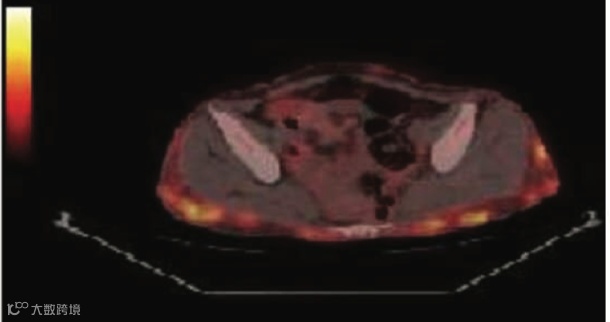

和老虎的条纹不同,雪豹的特点是全身布满了“圆点状、结节状” (Spotty/Nodular) 的高代谢灶。MIP 图上看,就像是一只潜伏在雪地里的豹子身上的斑点。

“豹纹”是皮下的结节。这种征象的核心定位在皮下组织(Subcutaneous tissue)和皮肤。它不是深层的肌肉,而是浅层的脂肪和软组织。